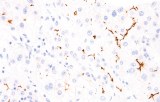

- In gastrointestinal stromal tumors (GISTs), KIT (CD117) expression is reliably detected by IHC, while PDGFRA mutations are evaluated through molecular testing, aiding in targeted therapy decisions.